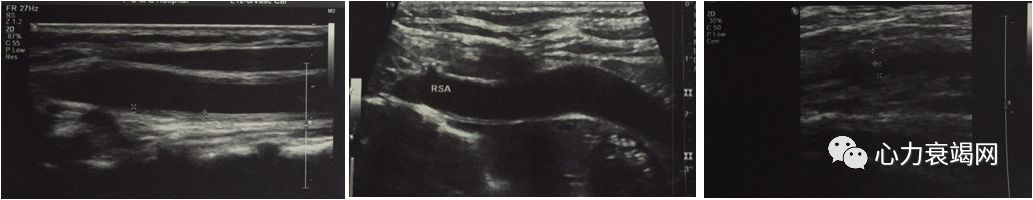

治疗前

胸闷明显好转、无咯血,可以平卧,平地活动不受限

2个月后

激素及抗心衰治疗后